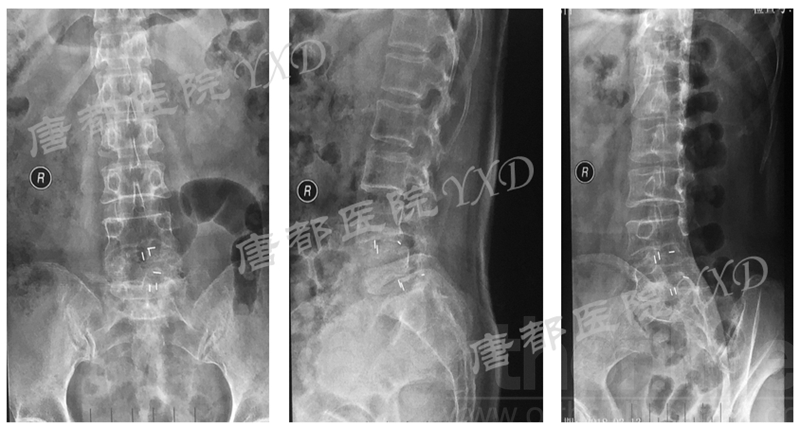

患者60岁,女性。

主诉:腰椎术后左下肢疼痛9月、加重4月。

专科情况:轮椅推入病房;强迫体位;双侧直腿抬高试验、加强试验阴性;左小腿后、外侧及足背、足底皮肤感觉减退;余未见明显异常。VAS评分:左下肢7。

既往8年前因“腰4、5椎弓峡部裂并腰4椎体滑脱症”于外院行腰4~骶1椎板减压椎间植骨融合内固定术,后因椎弓根螺钉断裂于5年前行内固定取出术。

影像学检查:

诊断:腰椎椎间融合术后融合器后移

手术方案:显微镜辅助MI-TLIF腰椎翻修术

术中视频:http://api.orthonline.com.cn/attach/Case3.mp4(术中发现因前次手术全椎板及关节突切除,TLIF的第一步,即关节突关节的定位落脚点难以找到。显微镜下通过Kambin三角解剖位置,进行从外至内的解剖,寻找cage尾端;此外,因大量瘢痕渗血,难以进行充分止血;但在显微镜的照明和放大视野下,操作均可在不伤及神经的前提下进行。由于终板骨质吸收,椎间隙塌陷,导致术野内可同时看到出行根和走行根。而在显微镜下,能够通过调整景深和视线角度,精准充分处理椎间隙骨性终板。无手术并发症)

术后疗效:VAS左下肢1分、腰1分;左侧直腿抬高试验、加强试验阴性。